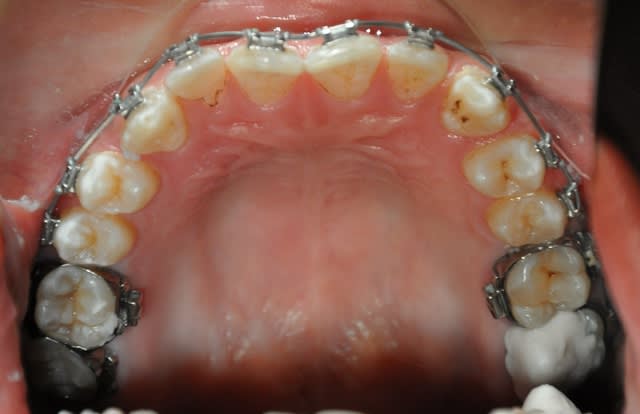

2ème étape

3ème étape,déjà postée